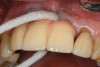

Locally delivered, controlled-release agents are a popular treatment adjunct and serve to augment scaling and root planing to help improve outcomes. Clinical studies have shown that use of such agents can provide an average of 0.5-mm additional pocket depth reduction over scaling and root planing alone, so the practitioner must weigh the cost-benefit ratio of using these products in each patient situation.39,40 A guideline for the appropriate use of locally delivered antimicrobials has been provided by the American Academy of Periodontology.41 These materials are contraindicated in patients with (1) multiple 5-mm pocket depths in one quadrant; (2) anatomic defects caused by periodontal diseases (intrabony defects); and (3) when the previous use of locally delivered agents has failed to control disease. As noted before, a follow-up reevaluation always should be completed to evaluate the success of any therapeutic intervention, generally at 4 to 6 weeks after treatment has been rendered30,31 (Figure 3A through Figure 3D).

Figure 3c  The site was treated by localized scaling and root planing, followed by use of Arestin (minocycline microspheres).

Figure 3c

Figure 3d  The resolution of inflammation and bleeding on probing on the reevaluation appointment 6 weeks later.

Figure 3d